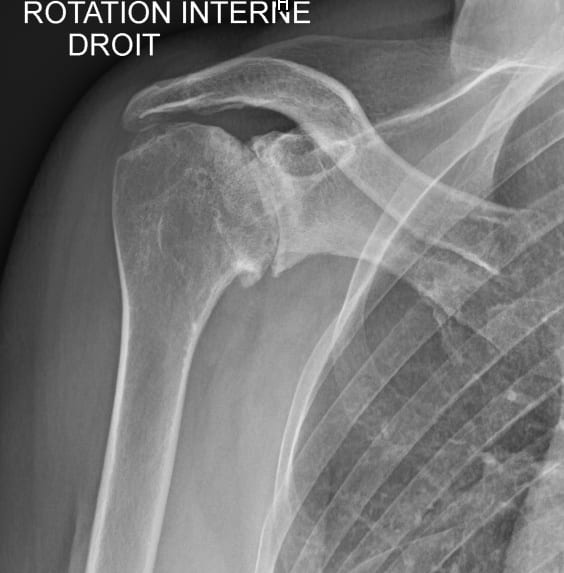

Omarthrose excentrée de l’épaule

Les radiographies standards sont souvent suffisantes pour poser le diagnostic d’omarthrose. Elles permettent également de préciser s’il s’agit d’une omarthrose centrée c’est-à-dire primitive ou d’une omarthrose excentrée liée à une rupture ancienne de la coiffe des rotateurs qui entraîne une ascension de la tête humérale vers l’acromion. Elles permettent également de localiser la présence d’ostéophytes qui sont des excroissances osseuses générées par l’arthrose, de visualiser du matériel chirurgical (clou, plaque, vis) liés à une intervention précédente pour une fracture par exemple.